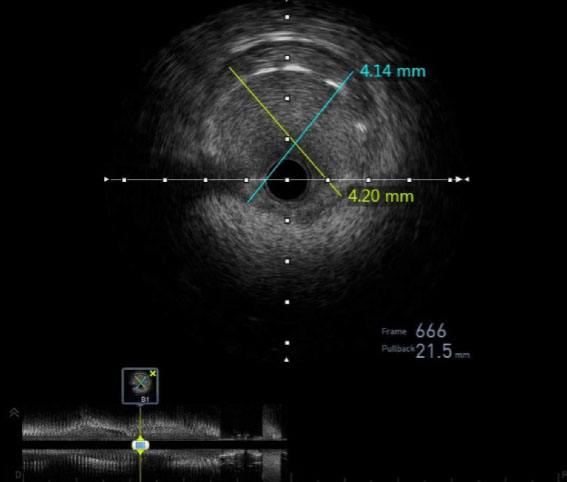

He was given 325 mg of aspirin, started on a heparin drip, and admitted. Cardiac catheterization showed severe high-grade narrowing of the proximal left anterior descending (LAD) artery (>90% stenosis), just after the branch point of the left circumflex (LCx) artery. The distal LAD vasculature was mildly hypoplastic, secondary to underfilling (Video 1). The right coronary artery was widely patent with no obvious lesions. Intravascular ultrasound (IVUS) revealed a thickened intimal wall at the level of the lesion consistent with an eccentric atherosclerotic plaque (Figure 2). The patient was transferred to an adult cardiac center where two drug eluting stents (DES) were placed in the proximal LAD to prevent further myocardial ischemia, as the artery was largely occluded. No intracoronary nitroglycerin was administered prior to DES placement. Intravascular ultrasound confirmed excellent position with 10% residual stenosis (Video 2). No biopsies were obtained due to the risk of inciting a ventricular tachyarrhythmia. He was discharged the following day on lifetime aspirin, ticagrelor for one year, metoprolol succinate, and rosuvastatin.

Figure 2: Pre-stent intravascular ultrasound (IVUS). IVUS revealed a thickened intimal wall at the level of the lesion consistent with an eccentric atherosclerotic plaque.

Cardiac manifestations of HSCT or GVHD may be related to chemotherapy toxicity, direct radiation exposure to the chest, or immune-mediated therapies. Similar to previous reports of ACS in patients with chronic GVHD, our patient had previous exposure to anthracyclines, known cardiotoxic chemotherapeutic drugs. The patient was also taking sorafenib, a tyrosine kinase inhibitor. Sorafenib been shown to lead to cardiac events including ACS, but without evidence of atherosclerotic disease [12]. Only one case of atherosclerosis has been reported in an adult patient treated with sorafenib and none have been reported in the pediatric population [13]. In our case, no coronary biopsies were obtained, limiting our ability to examine the coronary vessels and underlying pathology of luminal narrowing. Nonetheless, intravascular imaging was significant for intimal wall thickening, which suggests GVHD contributed to the development of CAD.